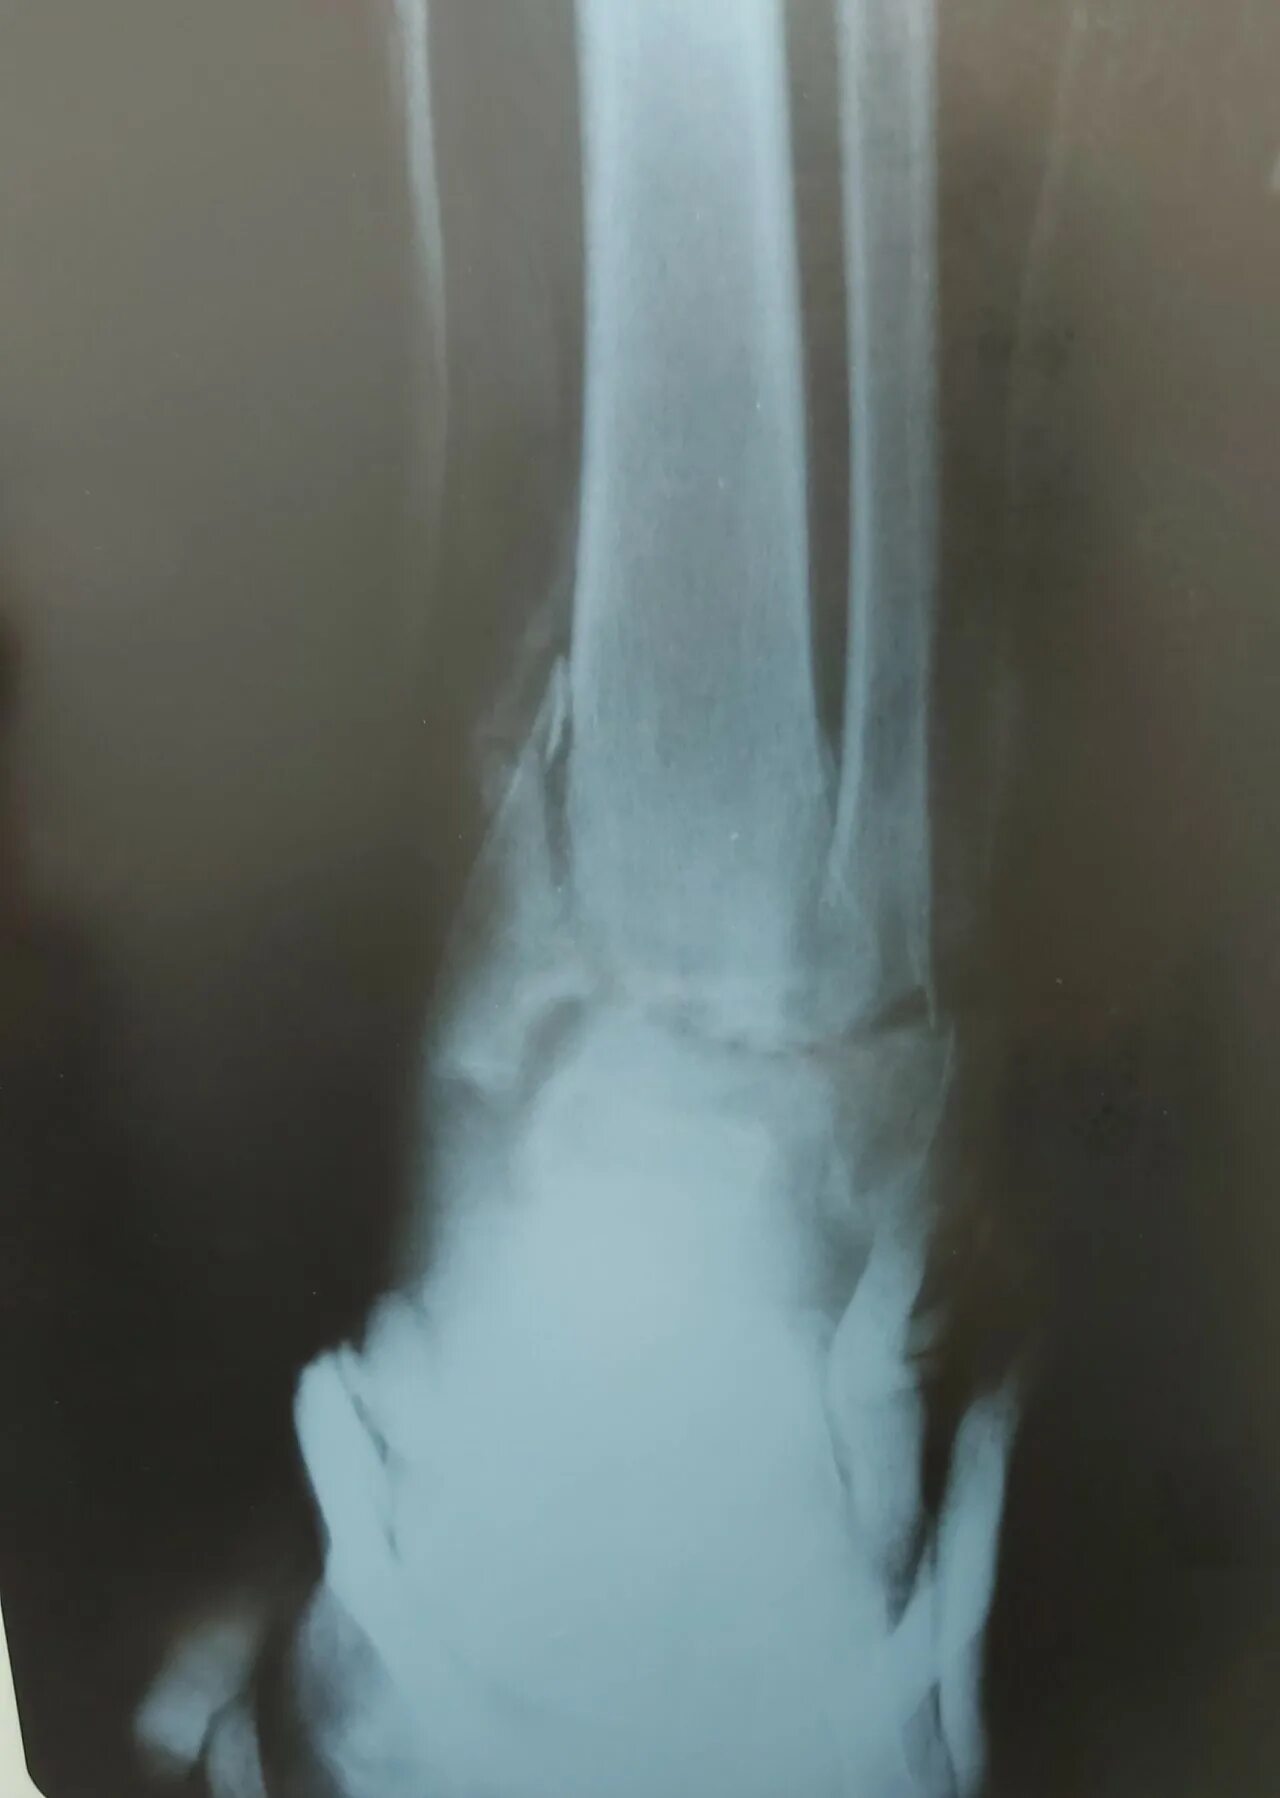

Через сколько срастается перелом лодыжки